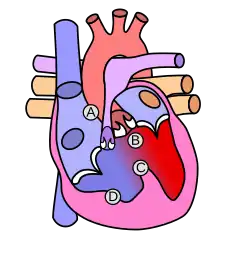

Четыре анатомических компонента:

- Вентрикулосептальный дефект — дефект межжелудочковой перегородки (ДМЖП) — соединяет между собой правые и левые отделы сердца. ДМЖП при тетраде Фалло всегда большой и нерестриктивный. Как правило, это перимембранозный ДМЖП (англ. perimembranous VSD), мышечный ДМЖП (англ. muscular VSD), или юкстаартериальный (околоартериальный; лат. juxta — около, подле, рядом) ДМЖП (англ. juxtaarterial VSD).

- Обструкция исходящего отдела правого желудочка — происходит за счёт одной из перечисленных или комбинации анатомических компонентов. К ним относятся инфундибулярный (подклапанный) стеноз исходящего отдела правого желудочка, клапанный стеноз лёгочной артерии, обструкция за счёт гипертрофированного миокарда правого желудочка, гипоплазия ствола и/или ветвей лёгочной артерии [6].

- Декстропозиция аорты — аорта отходит частично от правого желудочка или кровоток в ней поддерживается доминантно за счёт работы левого желудочка.

- Гипертрофия правого желудочка сердца — гипертрофия мышечного компонента правого желудочка развивается с возрастом.